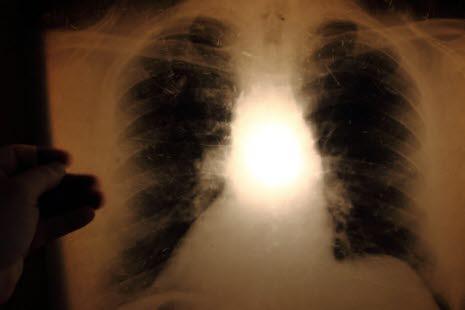

Tuberkulose er en livstruende infeksjon som først og fremst angriper lungene. Symptomer på aktiv tuberkulose er hoste, vekttap og slitenhet. Tuberkulose spres via dråpesmitte.

Tuberkulose er en livstruende infeksjon som først og fremst angriper lungene. Sykdommen dreper hvert år mellom en og to millioner mennesker rundt om i verden (i 2020 var det 1,5 millioner). Verdens helseorganisasjon (WHO) satser mye på å redusere forekomst og antall dødsfall forårsaket av tuberkulose.

Symptomer og tegn på aktiv tuberkulose er hoste, ufrivillig vekttap, feber og slitenhet. Selv om lungene er det organ som oftest er angrepet (lungetuberkulose), kan tuberkulose angripe også andre deler av kroppen som ledd, bein, urinveiene, sentralnervesysteet, muskler, beinmarg og lymfesystemet. Infeksjonen kan spre seg gjennom hele kroppen og angripe mange organsystem samtidig.